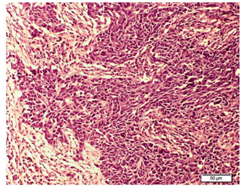

In the Histopathological examination of breast NETs resembles with lung and gastrointestinal NETs.2 According to the WHO, there are three histologic categories of breast NETs (solid carcinoid-like, large cell-type, and small cell-type).10 The growth of cells should be in solid sheets or insular pattern, presence of stippled chromatin and low grade cytological features.13 A histopathological examination of our patient made us consider the presence of neuroendocrine differentiation because the sections of breast nodule shows infiltrating tumor arranged in sheets and nests of atypical cells separated by fibrous bands and round to oval vesicular nuclei with powdery chromatin was seen. Further, the cytoplasm was scanty and frequent mitotic figures were present (Figure 6).

Figure 6 Photomicrograph of H&E stained section showing well stained tumor cells were present in breast tissue surrounding connective tissue.